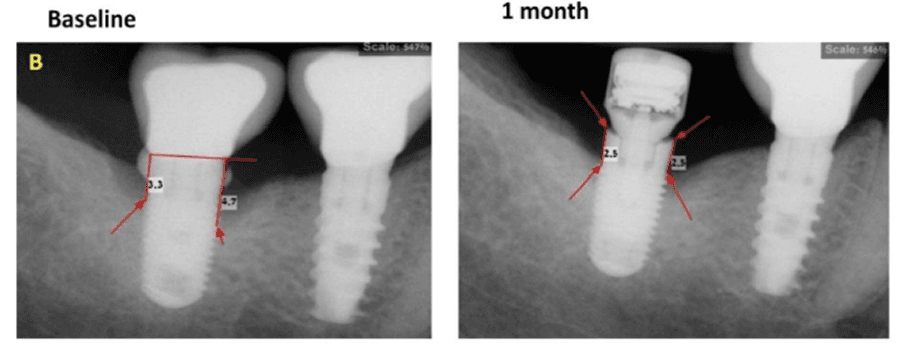

A 55-year-old healthy patient presented with inflammatory environment approximately seven years after successful implant placement. Radiographic evaluation revealed significant vertical bone loss around the implant, indicating advanced peri-implant bone resorption. A non-surgical regenerative protocol was initiated, consisting of removal of the prosthetic crown, deep mechanical debridement and curettage of the infected site, followed by the application of a MED healing abutment to stimulate local bone regeneration and reduce inflammation.

After only one month, radiographs demonstrated clear evidence of vertical bone regeneration around the affected implant, with visible bone fill in previously resorbed areas. The peri-implant tissue exhibited healthy tone and stability, with no bleeding or signs of inflammation. The regeneration process successfully preserved the implant, avoiding the need for complex surgical intervention or implant replacement. This case highlights the role of MED technology as an effective adjunctive treatment in the non-surgical management of inflammatory environment, promoting rapid bone healing and long-term implant stabilit